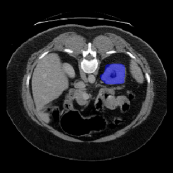

The predictions produced by the different prototypes are shown in Figure 6. Among them, in the segmentation of liver organs, it can be seen that the use of a single support prototype cannot produce a comprehensive segmentation, and the use of multiple support prototypes has significantly improved the effect, and the combination of multiple support prototypes and query prototypes can produce a more comprehensive segmentation. On the left kidney, the use of a single supporting prototype will produce a relatively large amount of over-segmentation, which will be reduced after the introduction of the query prototype, but some pixels are still over-segmented. However, the combination of multiple support prototypes and query prototypes can avoid over-segmentation.

SupportImg

QueryImg

SSP

MSP

SSP+QP

MSP+QP

GT